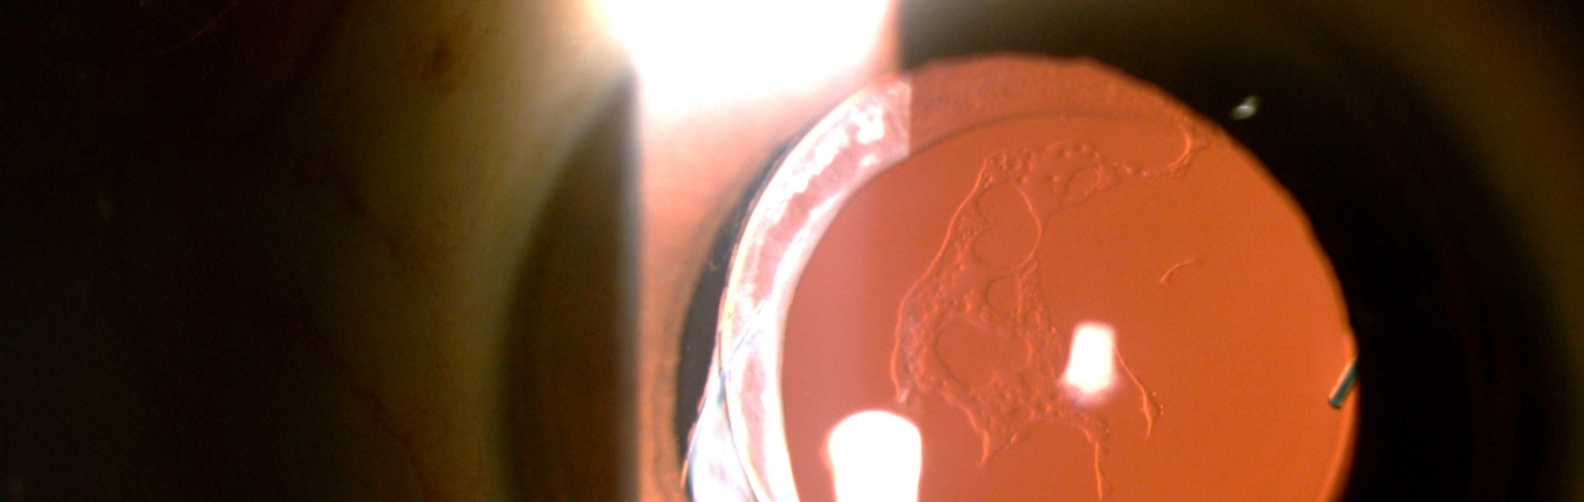

Elsching pearls, posterior capsular opacification American Academy of Posterior Capsular Opacification Glare posterior capsular opacification (secondary cataract) is a clouding of the thin membrane (lens capsule) that surrounds your newly. posterior capsule opacification (pco) posterior capsule opacification (pco) is a relatively common occurrence after. Pco can cause significant visual. Posterior capsular opacification (pco) is clouding that forms on the thin, natural capsule or. posterior capsule opacification (pco) is a. Posterior Capsular Opacification Glare.

Florid posterior capsule opacification in patient implanted with Sensar Posterior Capsular Opacification Glare what is posterior capsular opacification? posterior capsule opacification (pco) is a relatively common occurrence after cataract surgery but is easily treatable. posterior capsular opacification (pco) is a common complication of cataract surgery, causing. Pco can cause significant visual. posterior capsule opacification (pco) posterior capsule opacification (pco) is a relatively common occurrence after. Posterior capsular opacification (pco). Posterior Capsular Opacification Glare.

Eyes showing various forms of capsular opacification. (A) Extensive Posterior Capsular Opacification Glare posterior capsular opacification (pco) is a common complication of cataract surgery, causing. what is posterior capsular opacification? Posterior capsular opacification (pco) is clouding that forms on the thin, natural capsule or. posterior capsular opacification (secondary cataract) is a clouding of the thin membrane (lens capsule) that surrounds your newly. posterior capsule opacification (pco) is a relatively. Posterior Capsular Opacification Glare.